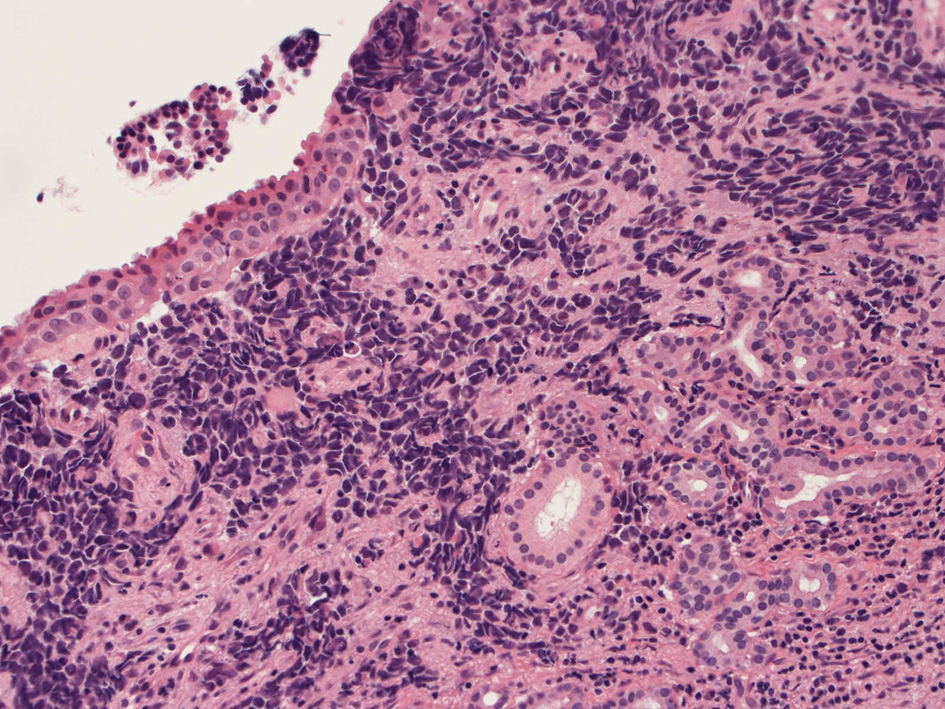

40歳女性 鼻粘膜腫瘤

右頸部のしこりを自覚。近医MRIで頸部多発リンパ節腫大あり当院を紹介される。右顎下, 右鎖骨上窩にも多数のリンパ節を触れる。穿刺細胞診ではcarcinoma疑い。右鼻腔, 上顎洞にも腫瘤が認められリンパ節腫大との関係を調べるために鼻腔腫瘤の生検が行われる。

病理組織所見

small round cell tumorの中でrhabdomyosarcomaは腫瘍細胞に種々の抗原が陽性となるため診断を誤ることがあり注意が必要である*1